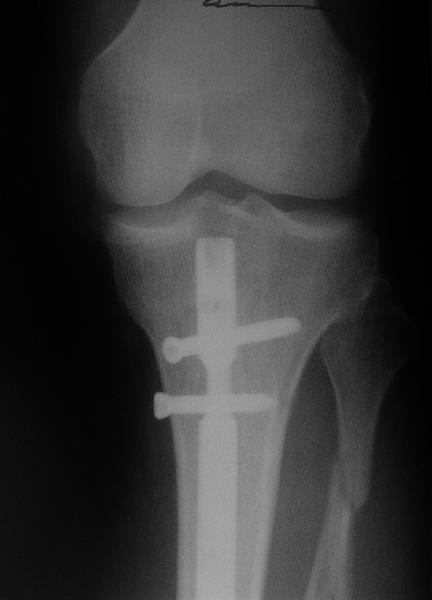

Стержень с большим диаметром и подлиннее?

С ходу не могу понять, почему неправильно фиксирован перелом.

Внизу стержень всего один статический винт держит?

Вальгус, стержень в дистальный отломок введен не на оптимальную длину. Такой диастаз будет долго заполняться, что чревато переломом стержня по ближайшему отверстию.

Вальгус сам по себе небольшой. Имеется промежуточный отломок, который не притянулся, так как отломки до конца не растянули. Сейчас наверное стоит подождать 2-3 мес. и посмотреть как пойдет срастание.

На снимке сохранен небольшой вальгус, но имеется нормальная аппозиция медиального кортикального слоя и поэтому трудно согласится что здесь имеется неправильно фиксированный перелом. Для идеального сопоставления таких косых переломов надо открывать фокус травмы, но тогда меняется философия фиксации.